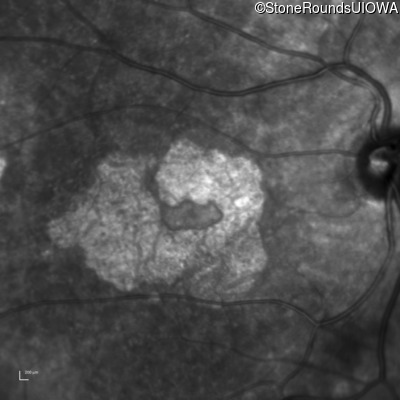

Infrared Fundus Photograph - Left - 20/125 -2

Exemplar